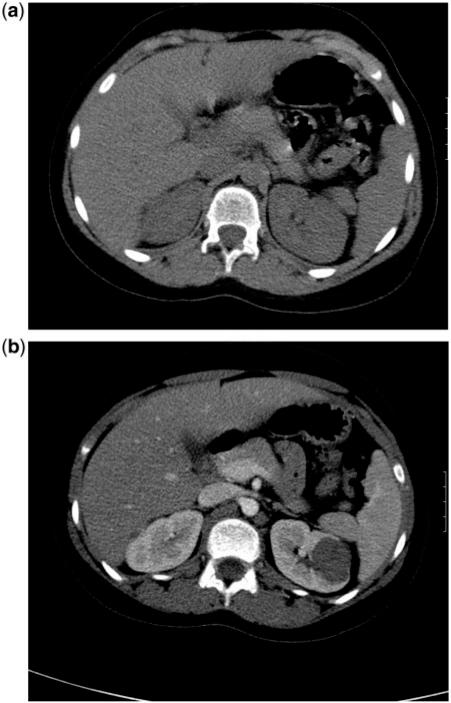

Enough literature now exists such that doing a non-contrast abdominal or chest computed tomography (CT) scan for suspected mass lesions in children borders on malpractice. Although there is great uncertainty regarding estimated radiation doses and long-term cancer risks in childhood, there is no doubt that an entirely unnecessary CT study does more harm than good. When a chest or abdominal mass is suspected in a child, only a post-intravenous contrast enhanced CT examination is needed, and a prior non-enhanced CT run exposes the child to unnecessary radiation.